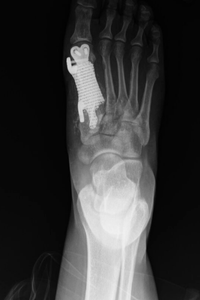

Her pediatrician thought otherwise and ordered X-rays, which showed a tumor on her right first metatarsal — the long bone that connects the big toe to the foot. Simrit had surgery to remove the tumor, and her biopsy results confirmed she had a condition called giant cell tumor of bone. This rare disease is known for coming back and can even spread from the bones to the lungs. Later scans showed Simrit had developed small tumors in her lungs.

With no off-the-shelf implant available, Dr. Kadakia would need to work with a manufacturer to design and 3D-print a new metatarsal. It was a somewhat experimental approach. “I’ve only read about one or two other cases in the country,” he explains.